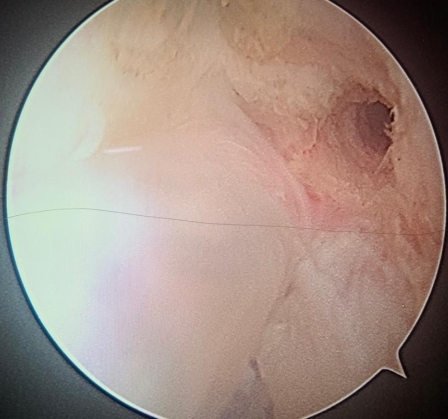

Physeal Sparing ACL Repair using Knotless Suture Anchor Technique for Pediatric ACL Injuries

Manit Arora , Frederick Weitz ………………………………p.57-60